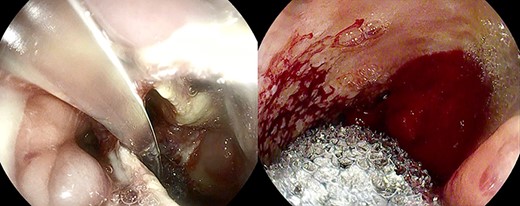

Anastomotic dehiscence was conservatively treated by EVAC therapy, placing the Esosponge in pleural space via an overtube (Fig. 2).